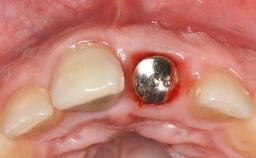

A 72-year-old female patient was referred to the specialist clinic with signs of peri-implantitis associated with implant 14. Two implants (sites 14 and 15) had been in function for three years. The patient was in good general health and was not taking any medication. She was a former smoker (12–15 cigarettes a day for 50 years) but had ceased smoking two years prior to implant placement. Her periodontal condition was stable, with no probing depths above 5 mm and a full-mouth plaque score (FMPS) of 35%.